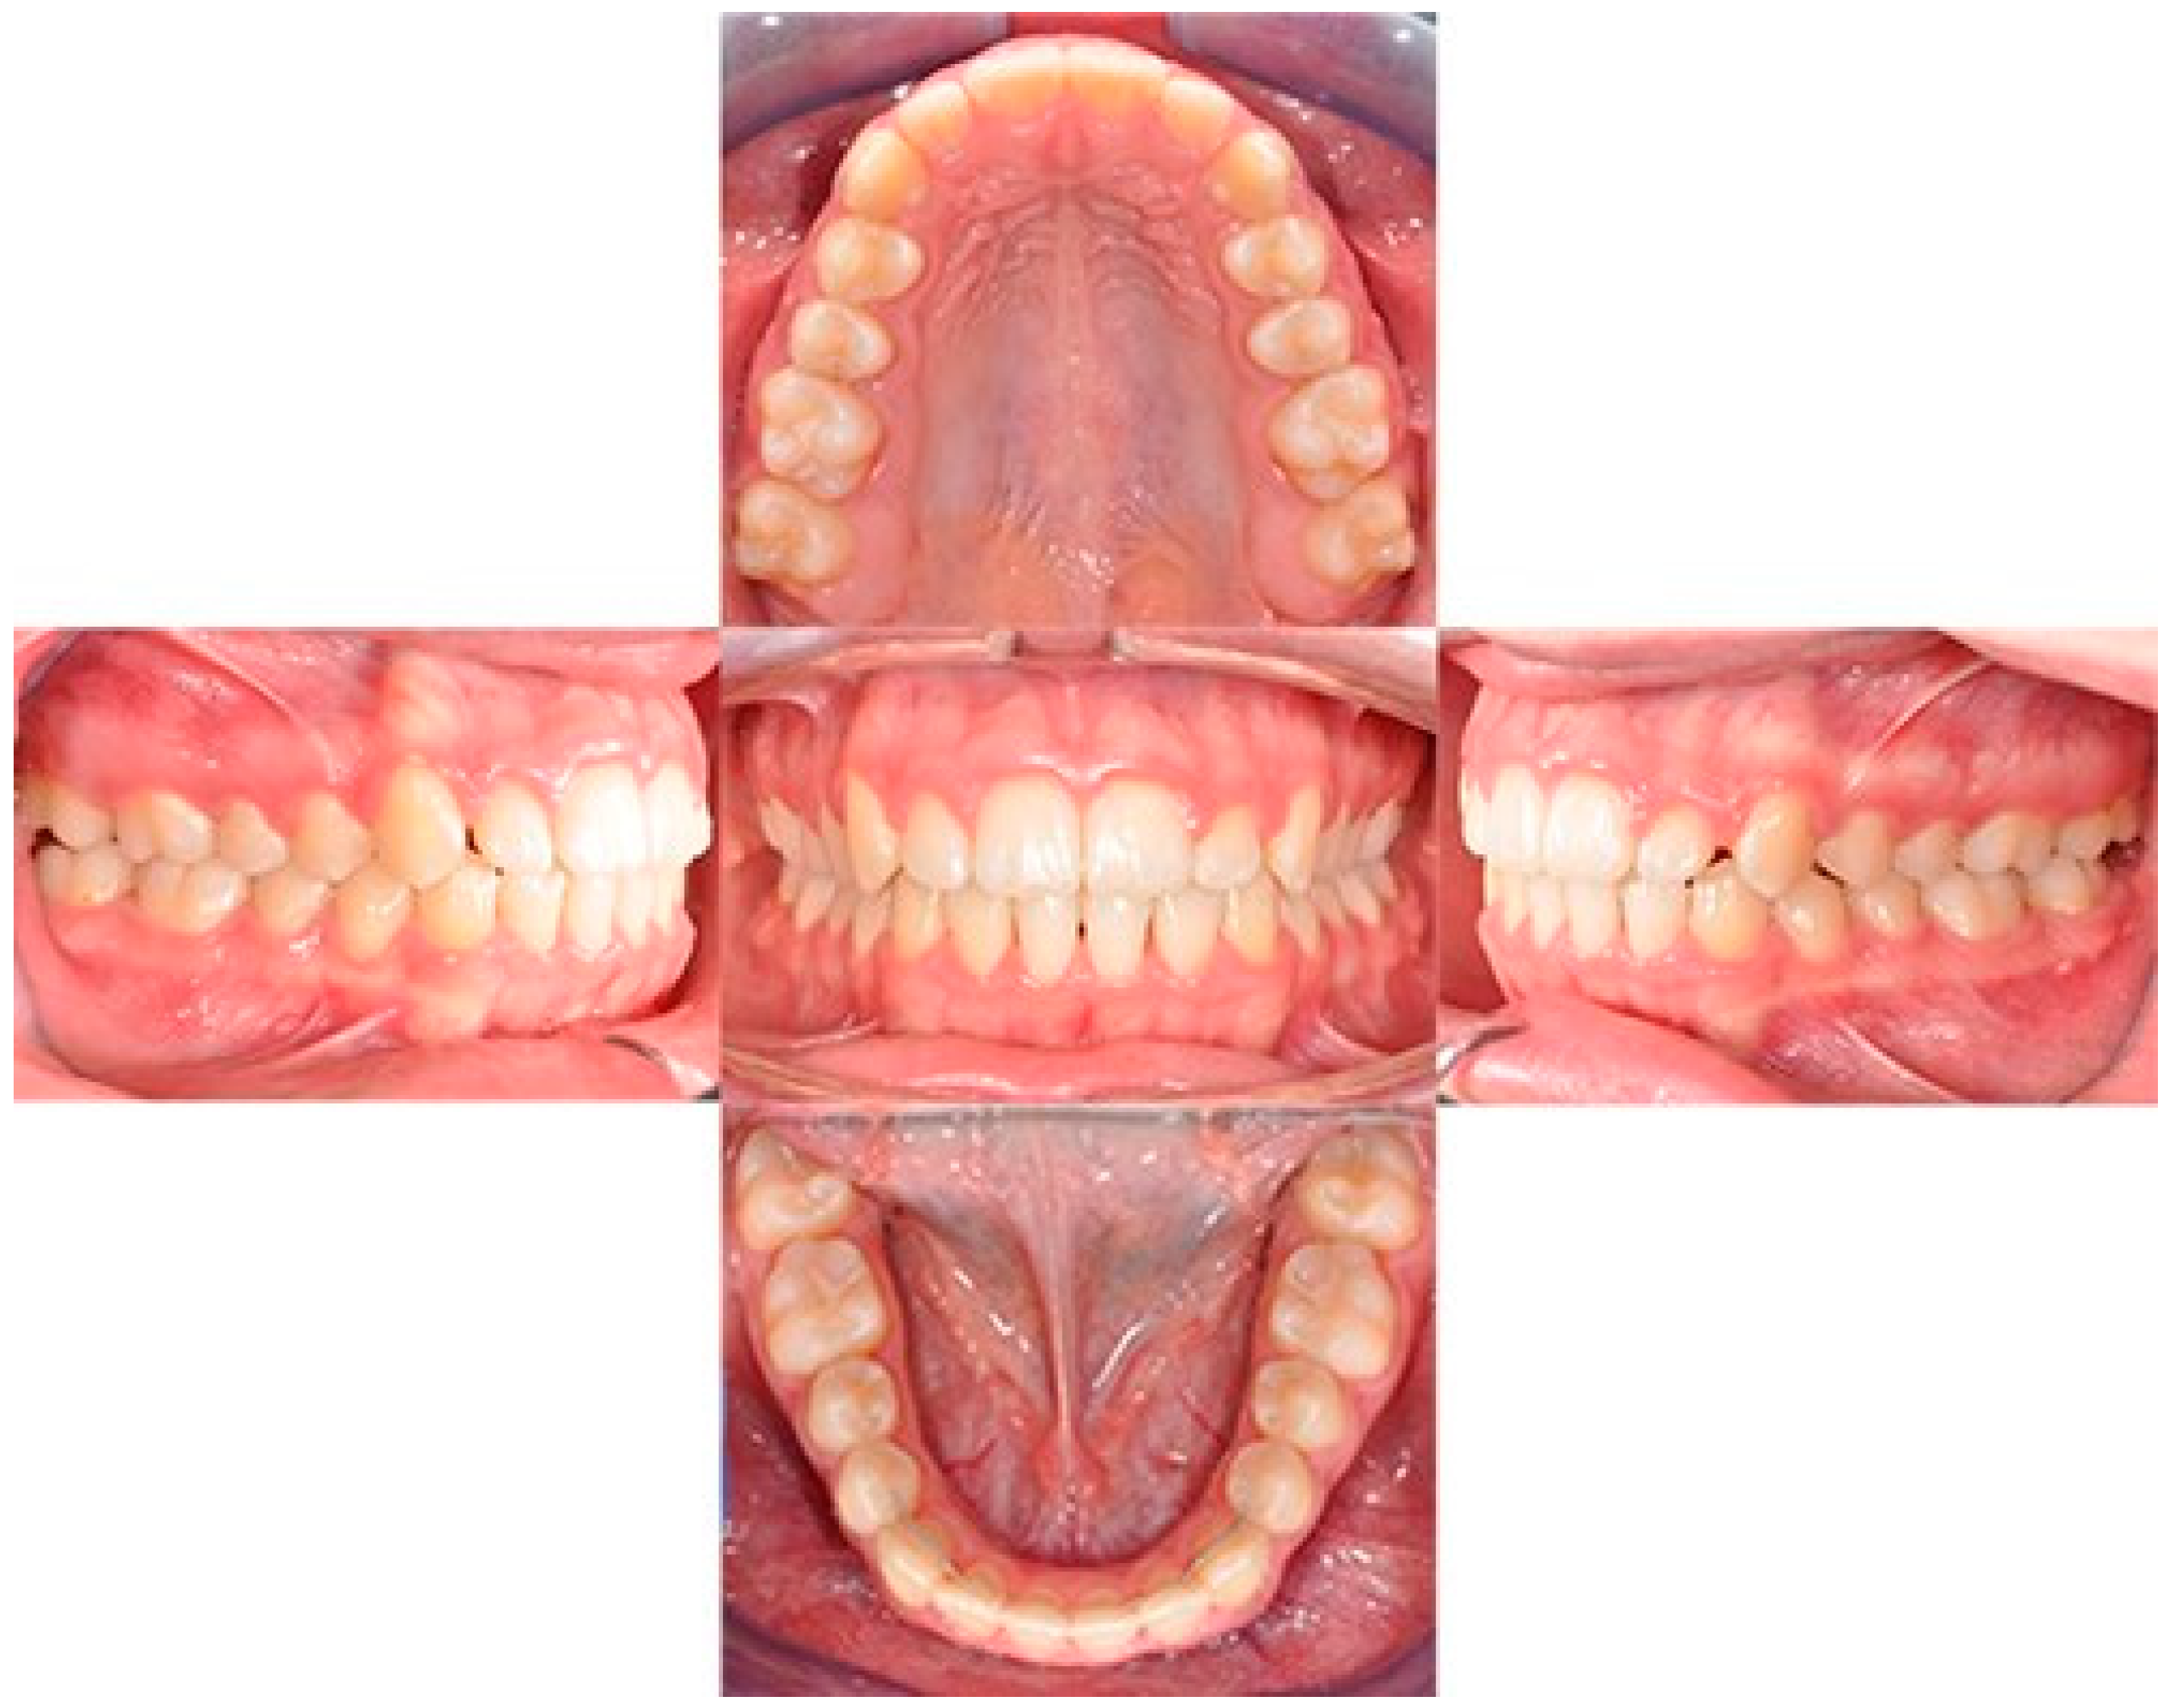

Figure 11. Final intraoral photos.

The treatment duration was 26 months. The post-treatment facial photographs showed a nicely balanced and harmonious face. A class I occlusion was obtained, and a distal space resulted in the upper incisors due to Bolton discrepancy. Prosthetic restoration was programmed to complete the patient’s smile. According to Table 1, counterclockwise rotation of the mandible was achieved (Figure 11, Figure 12 and Figure 13).